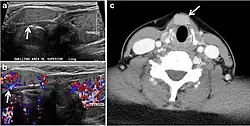

Ectopic thyroid tissue may be detected in the tongue near the foramen cecum (90%) and along the midline between the thyroid isthmus and posterior tongue, lateral neck, mediastinum, and oral cavity. The most frequent location is the base of the tongue (Figs. 16, 1717 and and18).18). In 70% of cases, the ectopic thyroid is the only functional thyroid tissue present in the body (Fig. 18).[1]

Fig. 17. Ectopic thyroid on the left parotid gland with a palpable left parotid mass in a 69-year-old male patient. a, b Axial and coronal enhanced neck CT scan demonstrates well-defined homogeneous enhancing mass (white arrows) within the left parotid gland with preserved surrounding fat planes. It also shows a normal thyroid in normal position in the lower neck. c Image taken 20 minutes after 5 mCi injected Tc99m-Pertechnetate shows normal thyroid uptake of tracer and physiological uptake in the salivary glands (short black arrow). There is a distinct focus of abnormal tracer accumulation in the left parotid/submandibular region. Patient was given lemon juice with evident normal washout from the salivary glands and relative retention by this abnormal focus (long black arrow).[1] -

Fig. 18. Lingular thyroid in a 33-year-old male who presented with oropharyngeal bleeding. an Axial enhanced neck CT scan at the level of mandible demonstrates a 3 × 3 × 3.4 cm round, partly well-delineated, heterogeneously enhancing lesion (white arrow). It is predominantly on the left side of the oropharynx and to some extent at the mid part of the base of the tongue. The thyroid gland was normal (not shown). b Image of the anterior face and neck taken 20 minutes after Tc99m-Pertechnetate injection shows absent thyroid radiotracer uptake in normal thyroid anatomical location (black short arrows). There is an area of increased uptake (long black arrows) corresponding to the posterior tongue mass identified on CT scan.[1]

Ectopic thyroid tissue lateral to the orthotopic midline location is rare. The exact anatomical definition of this rare entity is debated in the literature. To avoid confusion, some authors define a lateral neck ectopic thyroid as any thyroid tissue superficial to the strap muscles with no midline continuity. The majority of lateral thyroid ectopia cases have been reported as lesions closely related to the strap muscles. There are few reported cases of ectopic lateral thyroid tissue in the submandibular region, jugulodigastric region, or within the parotid gland substance (Fig. 17).[1]